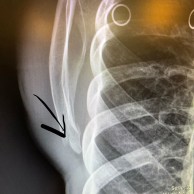

La ciclista Annika Langvad acaba de confirmar que se ha fracturado la mano y se ha fisurado el omóplato en una carrera local de MTB, categoría C1. Esta lesión no hace más que empeorar las cosas para la danesa, que hasta ahora no estaba teniendo un gran inicio de Copa del Mundo.

"Hasta ahora no podía decir que mi temporada de MTB de primavera hubiera ido sobre ruedas. Hoy me caí durante el calentamiento en una carrera local de C1 y me rompí al menos dos huesos en mi mano derecha más una pequeña fractura en el omóplato. Esto me obligará a estar 4 semanas con un yeso, pero debería poder subirme al rodillo y a la bicicleta de carretera mientras tanto. ¡Qué fastidio!"